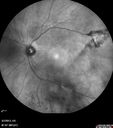

Prominent Posterior Hyaloid with Background Diabetic Retinopathy2401 viewsDiabetic patient comes in for follow up for her Background Diabetic Retinopathy and glaucoma. VA is 20/30. left eye. Fundus exam shows posterior Hyaloid with hemorrhage inferiorily.May 20, 2013

Prominent Posterior Hyaloid with Background Diabetic Retinopathy2710 viewsDiabetic patient comes in for follow up for her Background Diabetic Retinopathy and glaucoma. VA is 20/30. left eye. Fundus exam shows posterior Hyaloid with hemorrhage inferiorily.May 20, 2013